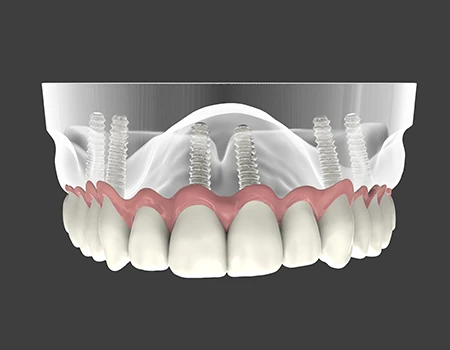

All-on-4 và All-on-6 là phương pháp cấy ghép Implant toàn hàm bằng cách sử dụng 4 hoặc 6 trụ Implant để nâng đỡ một hàm răng cố định.

Thay vì phải cấy từng trụ Implant cho mỗi răng, kỹ thuật này cho phép:

- Phục hồi toàn bộ hàm răng chỉ với một số lượng trụ tối ưu

- Giảm số lượng trụ Implant nhưng vẫn đảm bảo chịu lực và độ ổn định cao

- Có thể hạn chế hoặc tránh ghép xương nhờ kỹ thuật đặt trụ nghiêng thông minh

- Hàm răng cố định chắc chắn, khác biệt hoàn toàn so với hàm giả tháo lắp

- Trụ được đặt chính xác theo thiết kế, có thể đặt nghiêng để tối ưu xương